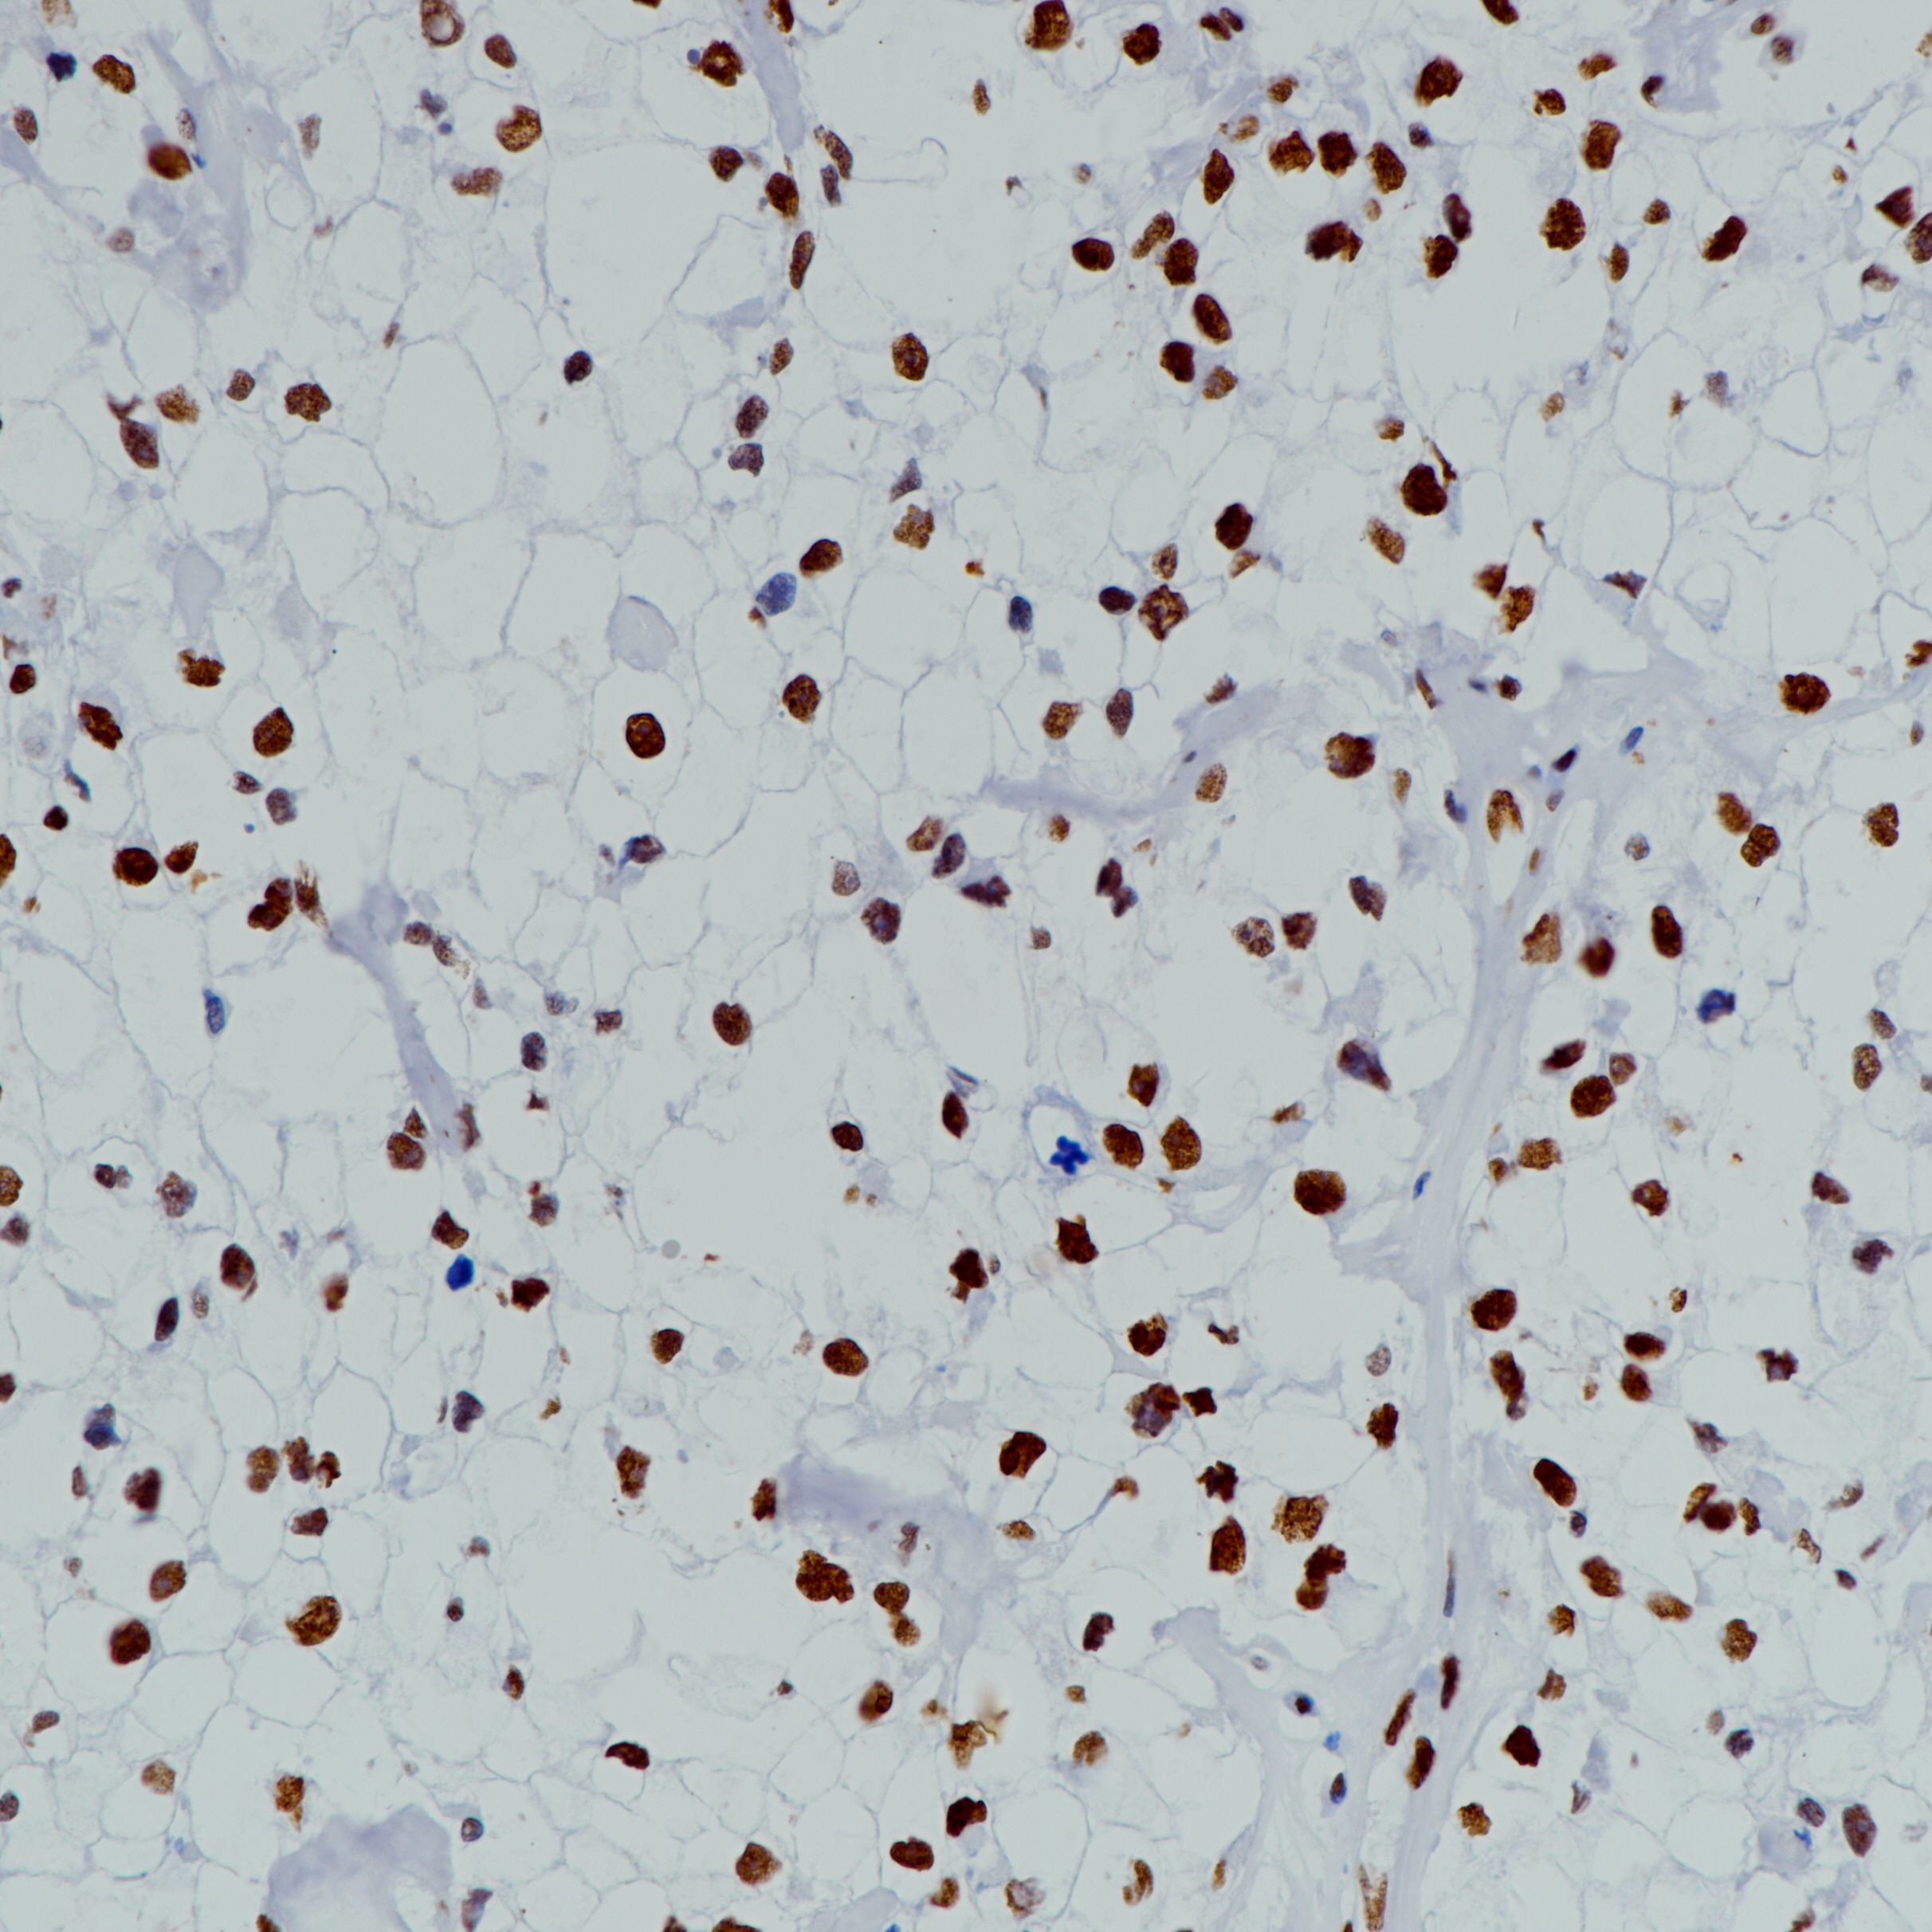

Cytokeratin 19(CK19) 重组兔单克隆抗体

细胞角蛋白19(CK19)是最小的角蛋白且非常罕见,因为它广泛缺乏所有其他角蛋白典型的非螺旋尾状结构域。它可能是由角质形成细胞角蛋白发展而来的。CK19在大多数简单上皮细胞中表达(不包括实质细胞如肝细胞,胰腺腺泡细胞和肾近端肾小管细胞),特别是在各种导管上皮细胞,小肠和大肠上皮细胞,胃小凹上皮细胞和间皮细胞中。此外,它存在于大多数假复层上皮细胞和尿路上皮细胞以及非角化复层鳞状上皮的基细胞中。在肿瘤中,CK19广泛表达于腺癌和鳞状细胞癌中,因此并不常用作癌分型的免疫组织化学标记物。CK19在大多数肝细胞中不表达,因此可用于鉴定肝转移,以及肝细胞特异性抗原的检测。

阳性对照

甲状腺癌